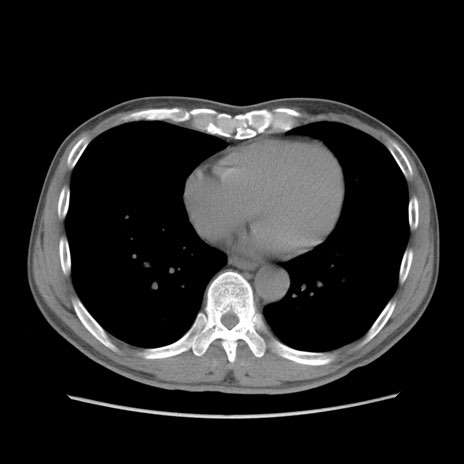

症例56 CT(横断像)

脂肪ウインドウ